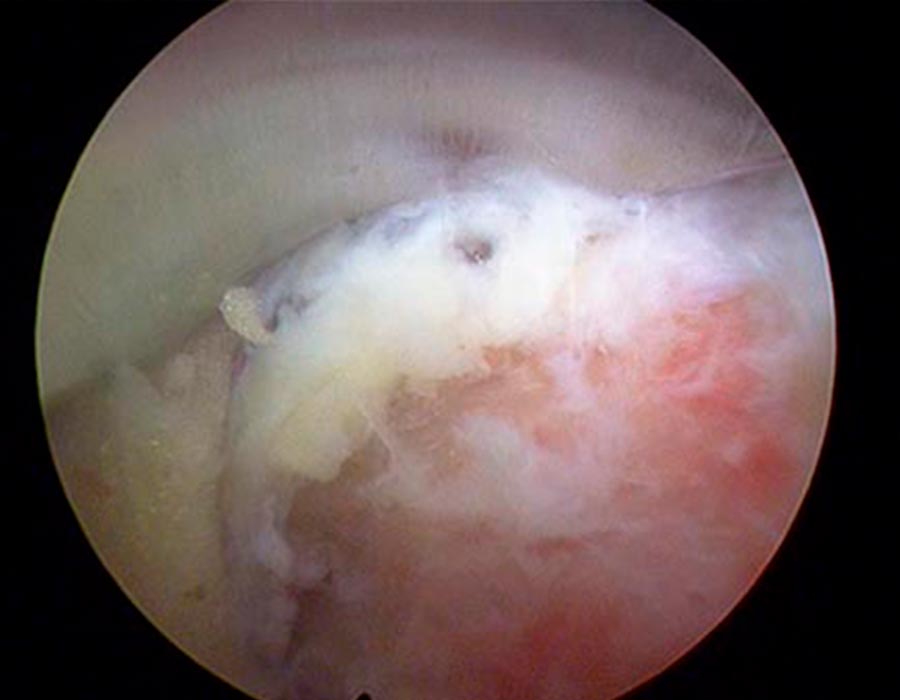

Para poder dar un diagnóstico observamos durante 6 meses la evolución de la paciente en el marco, y sobre la hernia foraminal L5-S1 y localizamos el problema. Presentaba una estenosis de canal entre las vértebras L4-L5 tal y como se puede ver en las siguientes imágenes.

Procedemos a la liberar de la estenosis el canal con mucha delicadeza y revisando que no quede ningún resto, todo ello mediante una incisión cutánea de 3mm muy precisa.

Tras realizar este vaciado comprobamos cómo queda adecuadamente liberadas las estructuras neurológicas vigilando que el espacio que queda ahora sea el correcto.